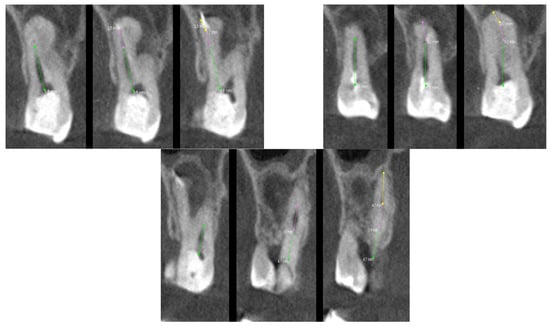

Figure 7 shows the analysis of the root canals in the transverse plane. Each image was analyzed separately. The colored lines indicate the canals visible on the scan. The plane was slowly moved with mouse clicks to show the subsequent sections of the canals, which were then marked with different colors. Each of the canals required the summation of at least two values to approximate the entire length of the root canal. The most complicated turned out to be the distal palatal canal, which required summing up the individual lengths from five scans. Table 2 presents the minimum number of scans for each root canal needed to analyze its entire course and shows the percentage of the length of the canal visible on the scan.

In the first case, the patient was referred to endodontic treatment, while in tooth 17, carious pulp exposure was detected. It was a deep subgingival carious lesion. Thus, the patient considered extraction and implant placement, and as a consequence, the patient was referred for microCBCT. Upon analyzing the scans together with the patient, a decision was made to perform endodontic treatment. On the CT performed, four roots with canals of significant curvature are visible. All four canals were chemomechanically prepared and filled. Finally, the endodontic treatment was successful. The procedure was performed without any complications thanks to the high accuracy of recognition of the course of all four tooth canals. The 3D of tooth 17 with carious pulp exposure was shown in Figure 8.

Figure 7. The CT scan of the tooth was used for the analysis of the root canals in the transverse plane, in the case of tooth 17 with carious pulp exposure.